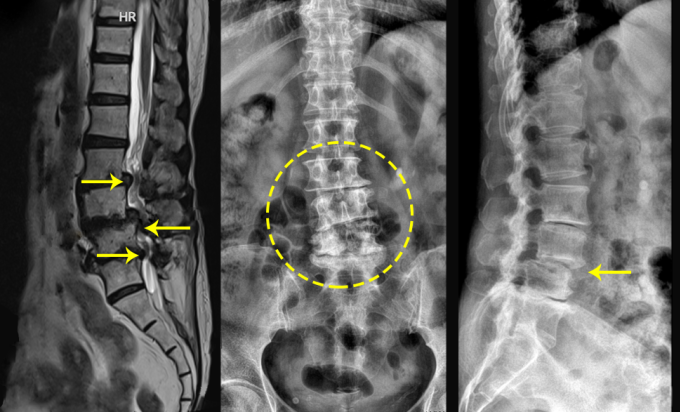

Bà Thanh từng trì hoãn phẫu thuật để điều trị nội khoa, tập phục hồi chức năng và châm cứu. Khi bà đến Bệnh viện Đa khoa Tâm Anh Hà Nội, bác sĩ chỉ định chụp X-quang, cộng hưởng từ MRI và đo điện cơ chi dưới. Kết quả cho thấy tủy sống bệnh nhân đã bị "bóp nghẹt", chèn ép thần kinh kéo dài gây yếu liệt. ThS.BS Nguyễn Bá Ba, khoa Chấn thương chỉnh hình, cho biết tổn thương này bắt nguồn từ tình trạng thoái hóa cột sống đa tầng rất nặng gây cong vẹo, trượt đốt sống, thoát vị đĩa đệm.

Bác sĩ Ba chỉ định phẫu thuật giải ép ống sống cho bà Thanh đồng thời đặt lồng liên thân đốt sống (còn gọi là thay đĩa đệm cứng), hàn xương liên thân đốt, bắt vít nắn chỉnh cột sống. Bác sĩ tư vấn cho bà ca mổ ứng dụng nhiều trang thiết bị hiện đại như máy định vị C-arm, kính vi phẫu... nên an toàn, giảm rủi ro tổn thương thần kinh nên bà đồng ý phẫu thuật.

Phần xương cắt bỏ được ghép trở lại cùng 3 đĩa đệm cứng liên thân đốt L2-3, L3-4, L4-5 để tạo thành khối vững, ổn định cột sống. Kế tiếp, bác sĩ sử dụng hệ thống vít và nẹp cố định titanium tương thích sinh học cao, bền vững, nắn chỉnh cột sống bị vẹo và đốt sống trượt cho bệnh nhân, đóng vết mổ.